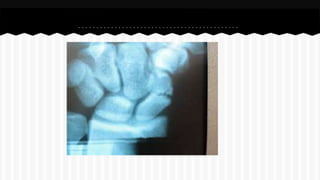

RESPONDA O NOME DO OSSO EM QUE

SE ENCONTRA A (S) FRATURA (A).